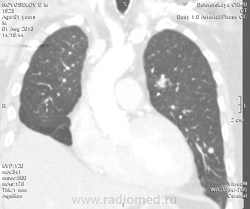

Мужчина оперирован по поводу BL щитовидной железы.Неоднократно проходил КТ в других лечебных учреждениях, у нас- впервые.Ставились заключения:MTS в лёгкие и лимф.узлы средостения слева.Образование слева увеличилось.Жалуется на одышку, не верит в заключение о MTS,просит узнать мнение других специалистов.

Метастазов в легкие не вижу. Похоже на лимфоузел в головке левого корня. Если позволите, запаздываете с началом исследования, плотность контраста в легочных артериях должна быть выше, чем а аорте. А одышка, не мудрено, легочная ткань диффузно уплотнена по типу "матового стекла", написал бы какую-нибудь интестициальную пневмонию, по типу альвеолита, может быть и гиперчуствительный пневмонит (не разберу есть или нет внутридольковые очажки), посмотреть бы изначально легочное окно, а не восстановленное из мягкотканного.

В диф. ряд: саркоидоз, атипичная форма.

Кажется,я понял,что Вы имели ввиду.Очажки стрелочкой указал.Согласен с тем,что очаги на фоне отображеничя сосудов кажутся фантазией,но они присутствуют.

Коллега, вынужден извинться и дезавуировать свой первый пост. Пересмотрел. Да, есть очаги, и они - вероятнее всего, метастазы.

Единственное,что напрягает,так это то,что эти изменения у пациента более 1,5 лет.А вид внешний у него не так уж и плох.А слева это всё-таки лимфоузел, а не периферическое образование в S3?